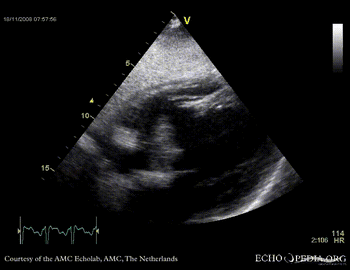

Rupture of the ventricular septum

VSR 4